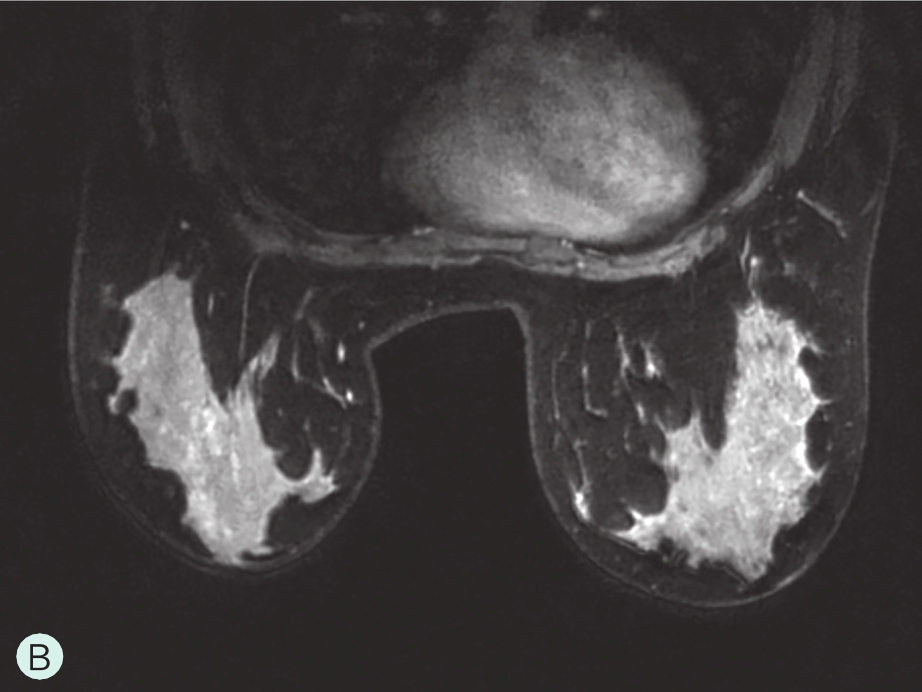

图1-4-4 增强MRI时不同乳腺腺体增强强度

A.MRI背景极少强化;B.MRI背景轻度强化;C.MRI背景中度强化;D.MRI背景重度强化